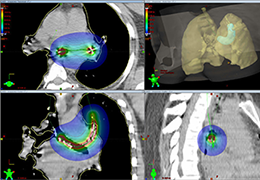

Parametric and non-parametric statistical maps may be superimposed both on the original functional scans as well as onto T1-weighted 2D or 3D anatomical reference scans. Time courses of selected regions-of-interest (ROIs) are available both in 2D and 3D representations. Statistical maps may be computed either in the 2D or 3D representation since structural as well as functional 4D data (space x time) are transformed into Talairach space. This allows you to compare activated brain regions across different experiments and across different subjects

Segmentation of tissue (e.g., isolating the brain, differentiating gray and white matter) is performed using region-growing methods, filter operations as well as the application of 3D templates. Using the mouse it is very easy to explore a 3D volume with superimposed pseudocolor-coded statistical maps in a four-window representation showing a sagittal, coronal, transversal and oblique section. Based on a (segmented) 3D data set a three-dimensional reconstruction of the subjects' head and brain can be calculated and displayed from any specified viewpoint using volume or surface rendering.

Volume Rendering

Volume rendering is performed with a very fast ray casting algorithm; lightning calculations are based on Phong-shading. Surface rendering of reconstructed surfaces is performed using OpenGL. Using texture mapping, a reconstructed surface (e.g., head or brain) may be sliced in real time, showing both surface and volume data at the same time. Initial polygon meshes serve as the basis for surface finding, cortex inflation and cortex flattening computations.